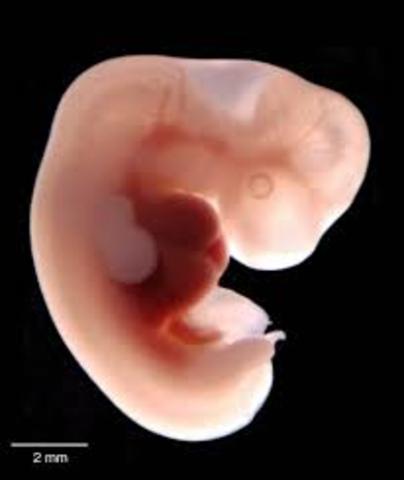

• Period of embryo

Period of embryo

3-8 weeks the umbilical cord extends from the embryo and connects to the placenta.The egg is fertilized. The amniotic fluid is beginning to collect around the ball of cells in the cavity that will become the amino sac.